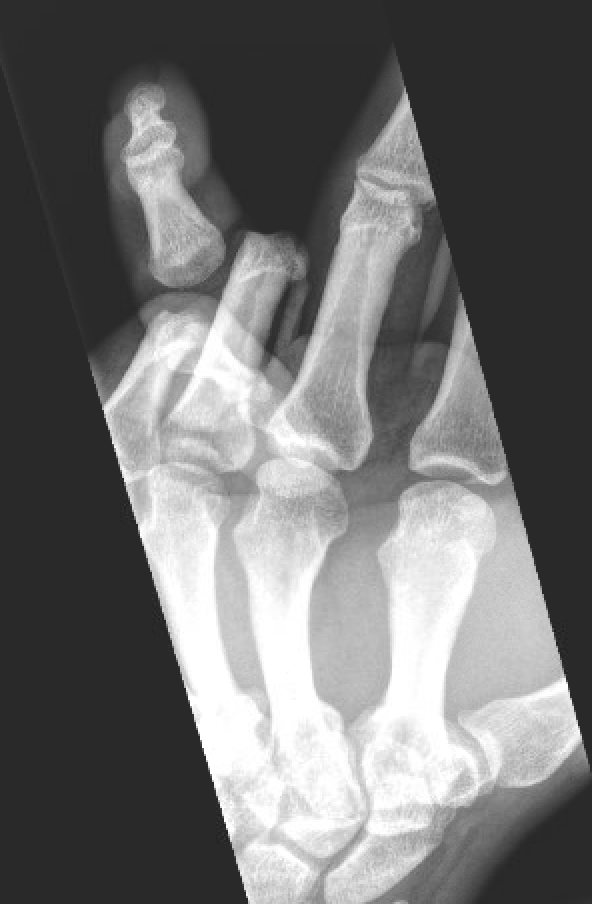

The images below demonstrate an open fourth digit proximal interphalangeal joint dislocation.

open finger dislocation open finger dislocation